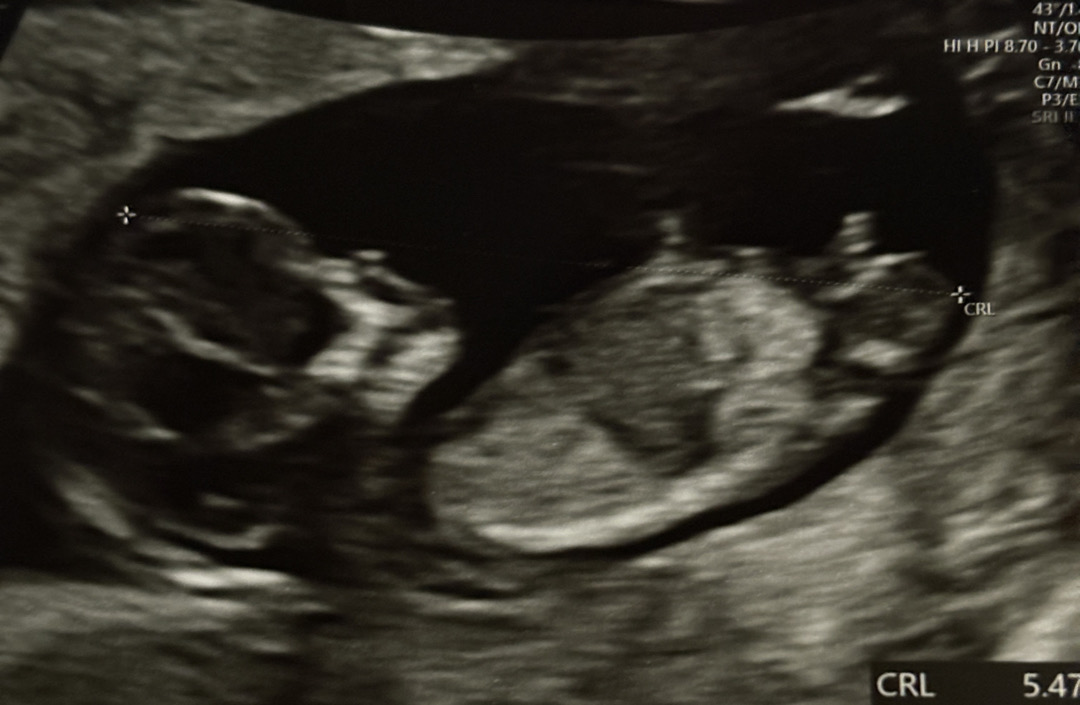

각도법 봐주세요..!!! 아무리 봐도 이해가 안가서..

지피티한테 물었더니 여자아이 같다는데 저는 보는 방법을 모르겠어요 😂